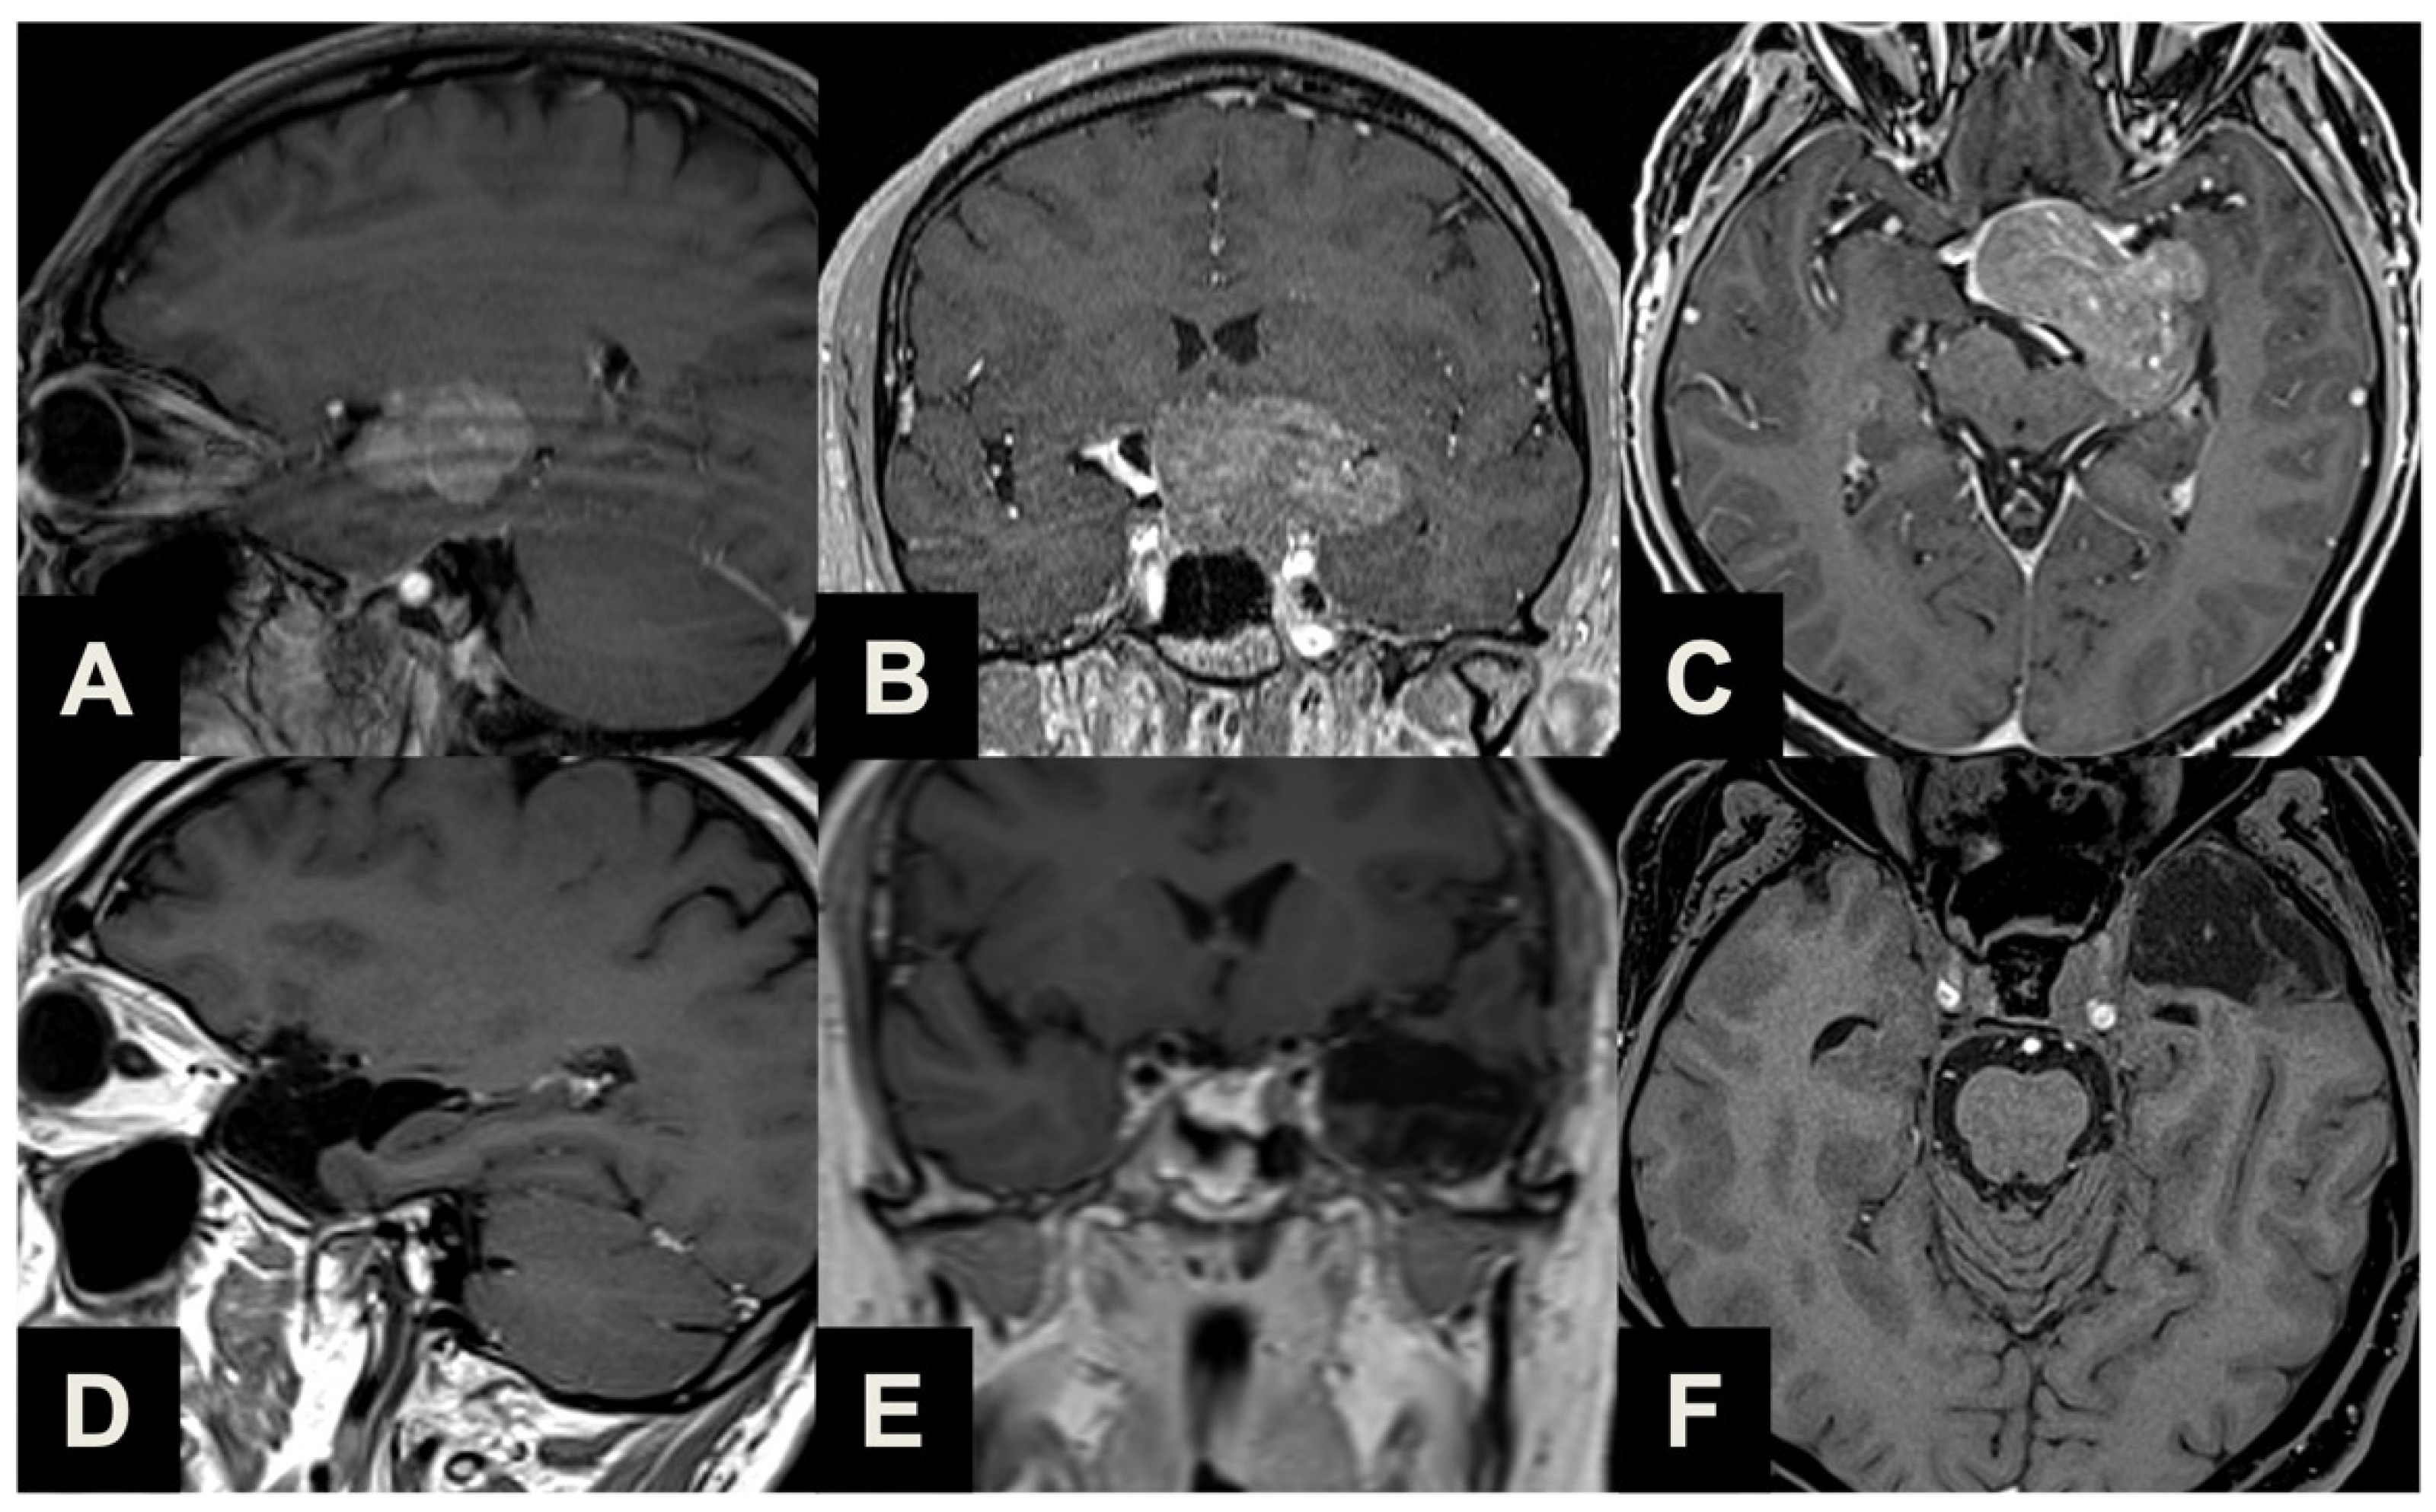

| Type 1 | Ectopic peduncular or supradiaphragmatic peri-infundibular PAs, including ectopic microadenomas of the pituitary stalk or purely supradiaphragmatic macroadenomas (mostly remnant or recurrence after previous partial surgeries). These tumors are not suitable for an EEA because they have no sellar infradiaphragmatic component. |

| Type 2 | PAs with sub-frontal extension, including macroadenomas with a supra- or infradiaphragmatic sub-frontal extension. These tumors are not fully resectable with an EEA because of their sub-frontal component, which extends anteriorly with an unfavorable angle and direction for the trans-sphenoidal approach. |

| Type 3 | PAs presenting with a major extrasellar component, including macroadenomas with suprasellar supradiaphragmatic component exceeding the sellar volume (i.e., air balloon PAs) unlikely to be delivered through the sella with an EEA, and macroadenomas with both a large intrasellar infradiaphragmatic part and a large suprasellar supradiaphragmatic portion connected through a narrow isthmus (i.e., snowman PAs), which impairs their resection through an EEA. |